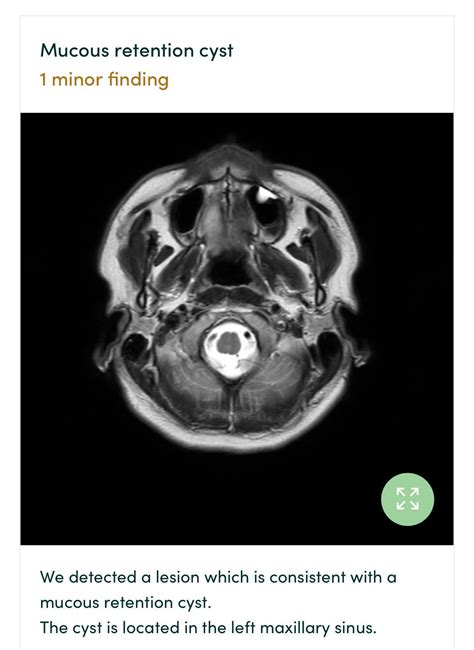

• Maxillary Sinus: Frequently discovered incidentally during routine dental X-rays or sinus scans.

In the sinuses, these are often referred to as antral pseudocysts. Unlike true cysts, which are lined with epithelial cells, many of these are "pseudocysts," meaning they lack a true cellular lining but function similarly in terms of fluid retention.

Maxillary Sinus Cysts:

• Usually produce no symptoms at all.

• They do not typically cause facial pain or pressure unless they grow exceptionally large.

• Often identified as a soft-tissue opacity on panoramic X-rays.

For sinus-related cysts, diagnosis is almost always incidental. If your doctor finds a "shadow" on your X-ray, they may recommend a follow-up CT scan to differentiate the cyst from a solid tumor or a localized polyp. Because these cysts are common, medical professionals are generally very adept at distinguishing them from more concerning growths.